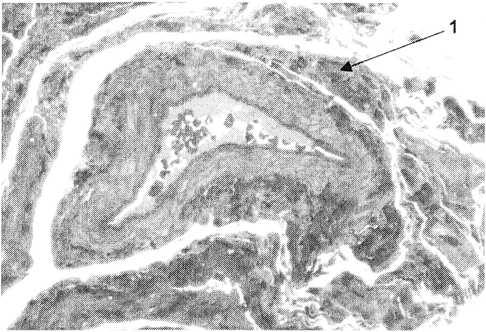

Рис.4. Гидросальпинкс.

Выраженный склероз крупных и мелких кровеносных сосудов, некоторые облитерированы. Мощные пучки коллагеновых волокон с большим числом фибробластов окружают их (1). Микрофотография полутонких эпоксидных срезов. Окраска: метиленовая синь, основной фуксин, увеличение × 125